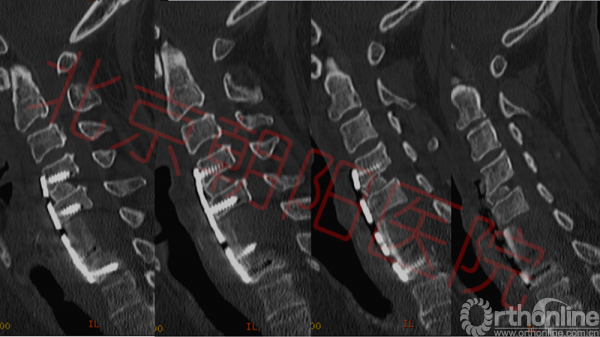

术后病理结果未见异常,细菌培养结果为耐甲氧西林金黄色葡萄球菌。继续应用利奈唑胺抗感染治疗。患者经术后3周抗感染及康复治疗,血常规、ESR、C反应蛋白PCT等感染指标恢复正常。上肢肌力较术前略有恢复,伸指肌、屈指肌、骨间肌肌力由I级恢复为II级;患者伤口愈合良好。术后2后复查颈椎CT(图4)显示植骨融合情况良好,颈椎核磁显示脊髓压迫解除。

图4:可见术后植骨融合良好